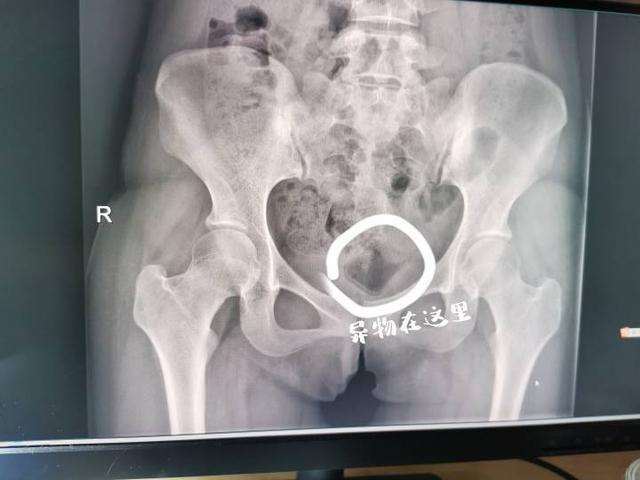

浙江19岁女学生和男朋友玩出新花样,将化妆品盖“遗留”在体内近一个月,女孩引发炎症,疼痛难忍,这才到医院进行就诊。

接诊医生经过查体后,确定小杨体内存在一个异物,该物体表面光滑,找不到着力点,凭借

普通医疗器械很难将其取出。并且因为物体在小杨体内留存时间较长,已经引起了炎症反应,下面已经有很明显的异味,随后预约了超声检查。